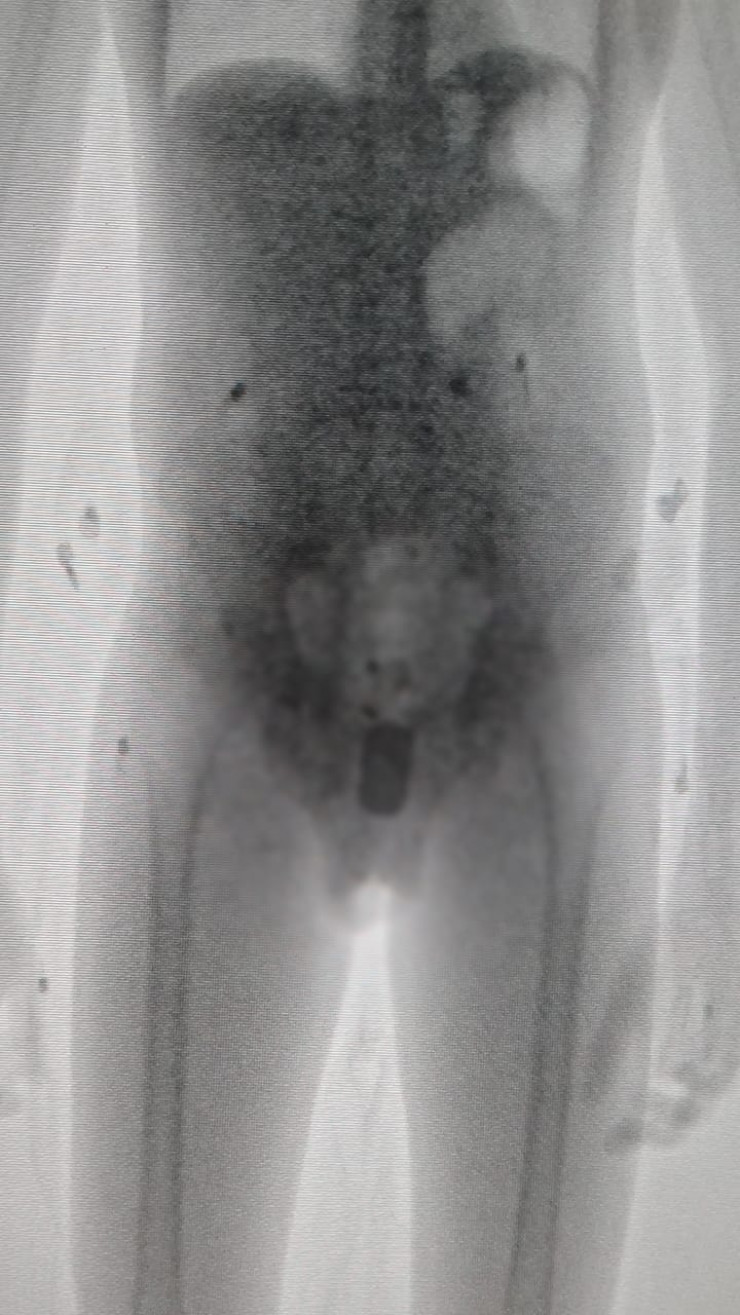

"Рентгеновский снимок показал, что, кроме телефона Nokia размером 6 сантиметров, там же была и действующая сим-карта", - сообщили в пресс-службе.